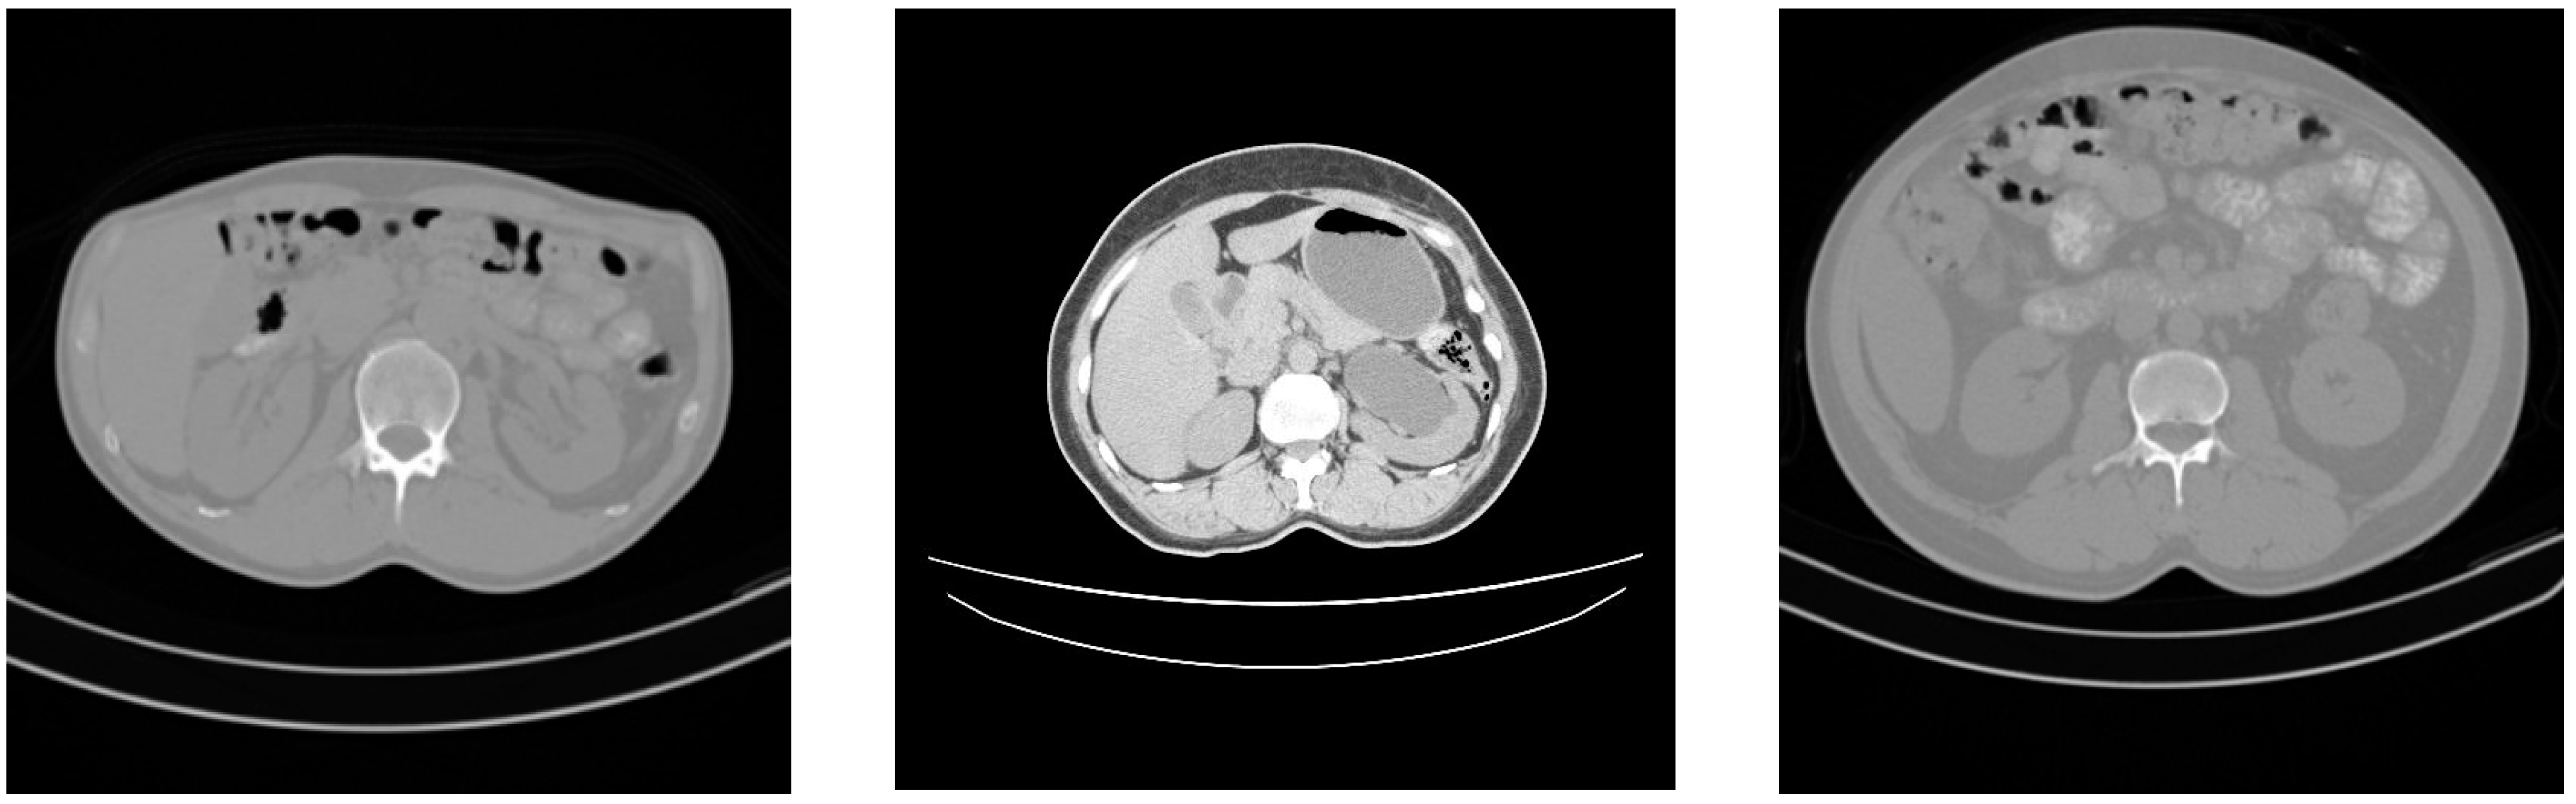

This prospective study included a total of 125 patients. The data set of 35 subjects (20 male subjects, 36 to 62 years old, mean age 49 years; 15 female subjects, 37 to 72 years old, mean age 51 years) was acquired using SIEMENS scanner at Country Heights Health Tourism Sdn. Bhd. Scanning was performed at 130 kV and 200 mA. The resolutions of the slices were 512 × 512 pixels, and the slice thickness was 2.5 mm in all subjects. The data set of the remaining subjects (57 male subjects, 24 to 72 years old, mean age 46 years; 33 female subjects, 26 to 70 years old, mean age 50 years) was acquired using a TOSHIBA scanner at the hospital of Serdang. Scanning was performed at 120 kV and 200 mA. The resolutions of the slices were 512 × 512 pixels, and the slice thickness was 2 mm or 3 mm. Both health centers are in the state of Selangor, Malaysia. The data set used is not publicly available due to the rights of Country Heights Health Tourism Sdn. Bhd and the hospital of Serdang located in Malaysia. Figure 1 shows some CT image samples from the employed data set.

Figure 1. CT image samples.